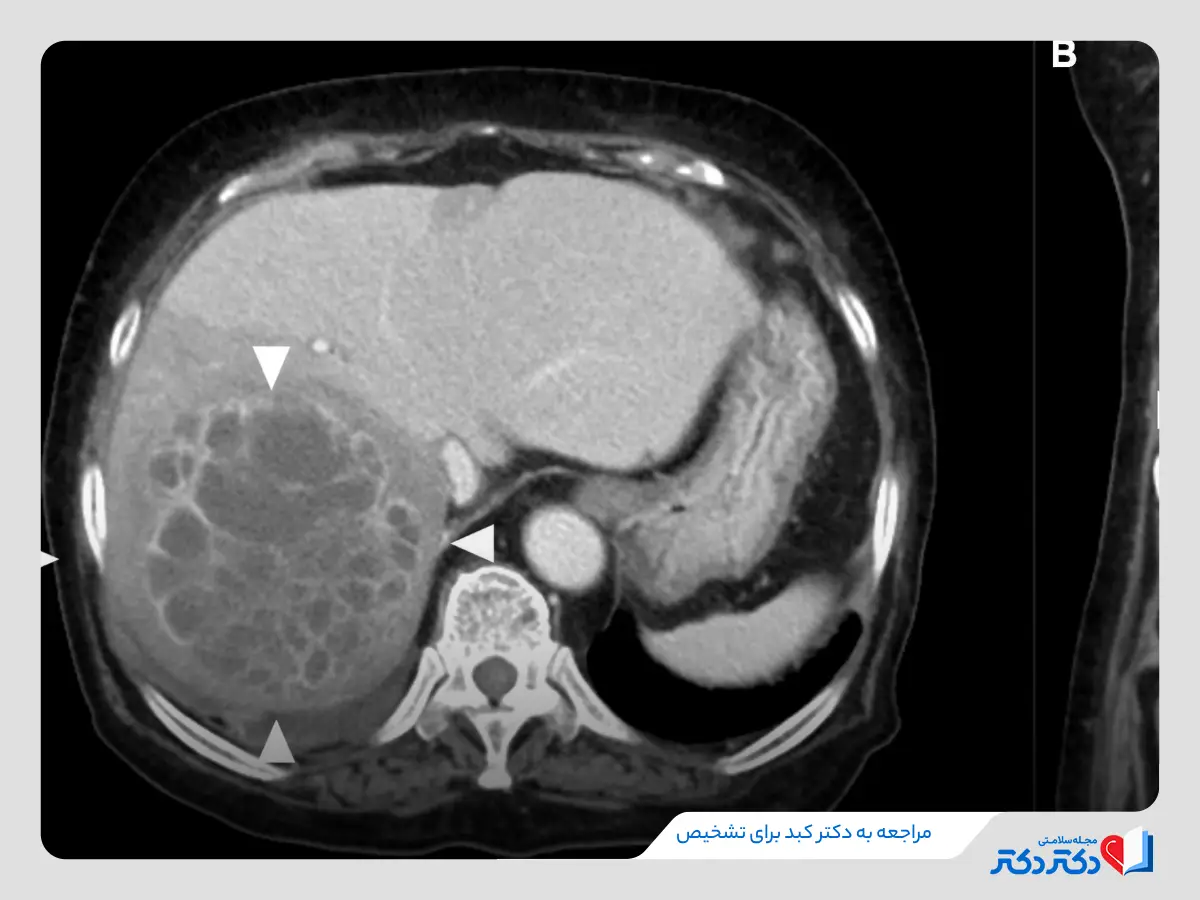

- انجام تستهای تصویربرداری شامل سی تی اسکن شکم، توموگرافی کامپیوتری با کنتراست و سونوگرافی کبد یا تصویربرداری رزونانس مغناطیسی (ام آر آی کبد)